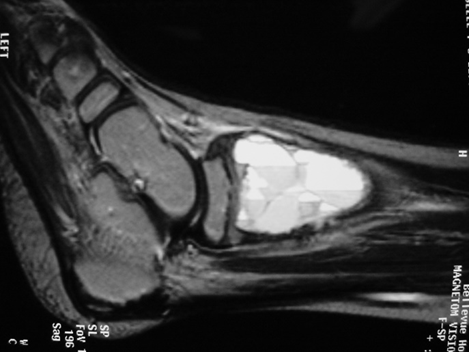

MRI

- Geographic well circumscribed

- High signal on T2 weighted MRI images

- Fluid/Fluid level (T2) are highly characteristic

Fig 2 a-e. MRI of an ABC of Distal Tibia: Fig 2 a-c: geographic cystic expansile lesion with fluid-fluid levels. The fluid-fluid levels are caused by bleeding into the cavities. The blood collects and the degredation products settle to the gravity dependent areas of the cavities. This shows up as fluid-fluid levels on the MRI. Fig 2 d,e: This is a gadolinium enhanced MRI of the ABC of the distal tibia. There is peripheral and septal enhancement indication cyst formation. The contrast outlines the cystic cavities but does not enter into the center